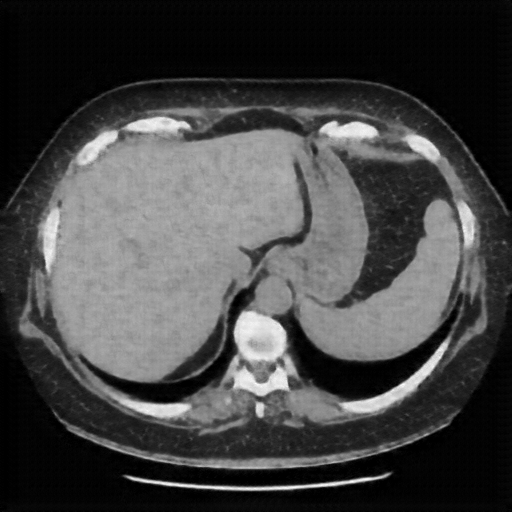

Generated VENOUS CT scan (A→B translation)

Full window (WL 1023.5, WW 4095 β†’ Low βˆ’1024, High +3071)

Actual HU range: [-1024.0, 695.6]